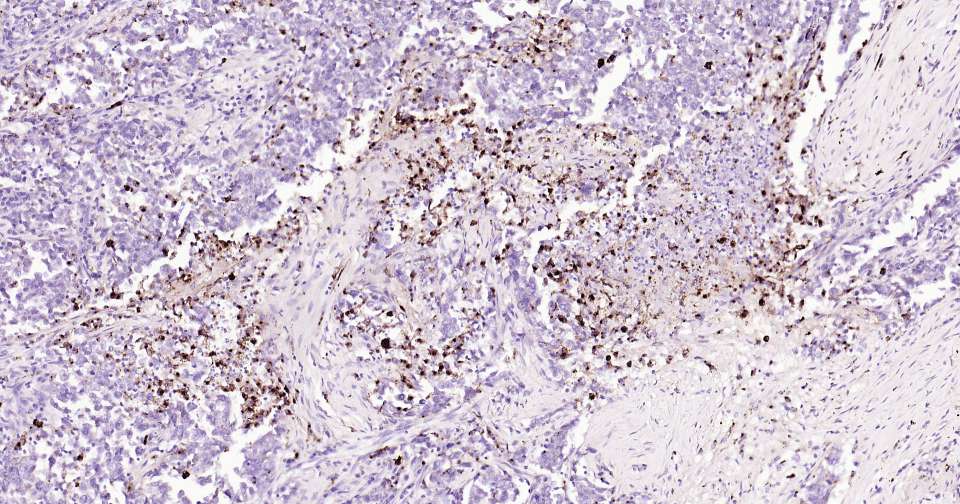

Immunohistochemical analysis of paraffin embedded human pancreatic cancer tissue slide using IHC0343H (Human Osteopontin Kit).